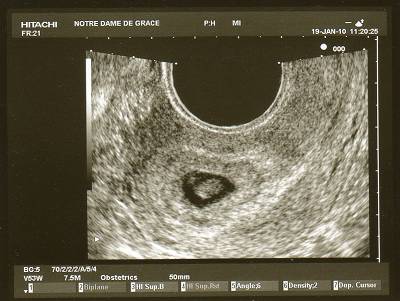

Visiblement, les decalages entre la date théorique de conception et la date réelle ne sont pas rares.

Tant que ton petit bout va bien, la date de la conception est un détail